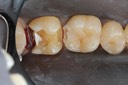

Kyle Chock #14 amalgam removal